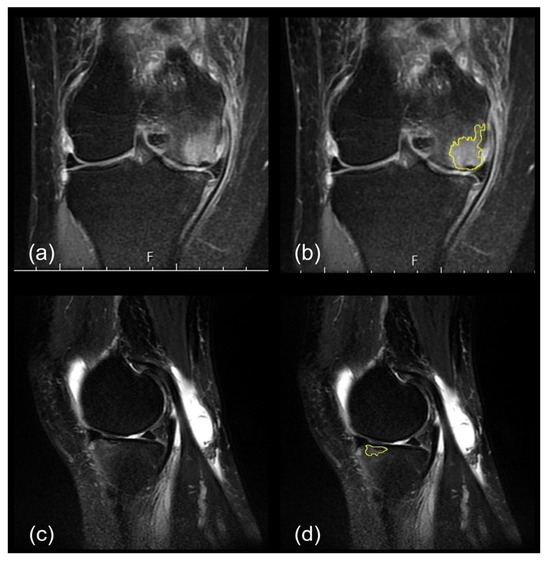

2.2.3. SIFK Identification

- The length units were calibrated using the 1 cm scale bar in the MRI images;

- An outline was drawn along the subchondral plate horizontally, and the flattened and depressed parts were connected;

- An outline was drawn along the thickened subchondral plate perpendicularly, without ill-defined areas, such that a radiating, disrupted linear pattern was obtained (Figure 2).